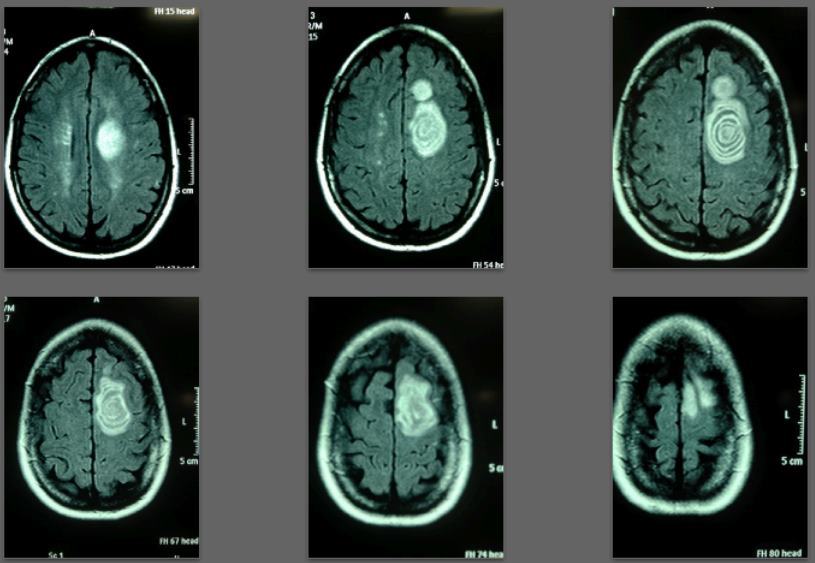

Before/after MRI images for one of 1,000+ patients of Dr. Coimbra

2008 Convulsive seizures Diagnosis: Balo’s concentric hemiparesis

Starting daily dose 25,000 IU; increased in stages to 80,000 IU on October 28, 2010. Asymptomatic since 2010.

2008 MRI